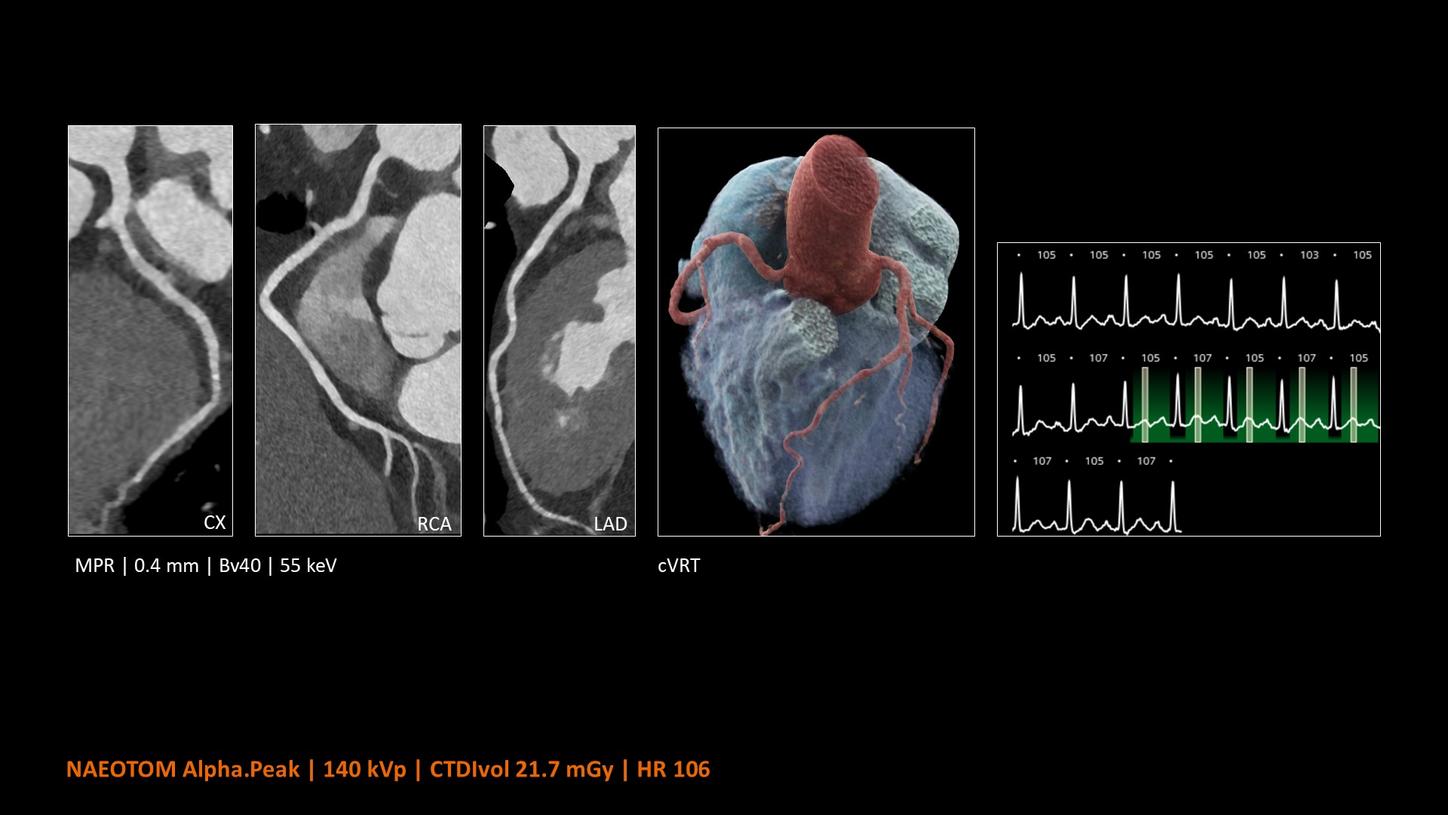

NAEOTOM Alpha® con Quantum Technology®, la nostra nuovissima Dual Source photon-counting CT, offre immagini Quantum HD Cardiac con uno spessore di slice di 0,2 mm. In questo modo è possibile visualizzare dettagli del cuore precedentemente non rilevabili senza incrementi di dose. Inoltre, le informazioni spettrali sono automaticamente disponibili in ogni scansione grazie a un processo di conversione diretta che trasforma i singoli fotoni dei raggi X in un segnale elettrico per creare l'immagine.

Quantum Technology consente una migliore valutazione diagnostica dei vasi coronarici nella TC. Secondo un recente studio, NAEOTOM Alpha e Quantum HD Cardiac potrebbero aver contribuito a ridurre la necessità di un'angiografia coronarica invasiva per il 54% dei pazienti nel rilevamento della malattia coronarica in una popolazione ad alto rischio.¹

Il Dott. Bálint Szilveszter, MD, PhD, presso la Semmelweis University a Budapest, in Ungheria, condivide I benefici dell’elevata risoluzione spaziale e della valutazione della placca con la TC photon counting e come questi permettano una maggior confidenza diagnostica nella valutazione dei disturbi alle coronarie (CAD)